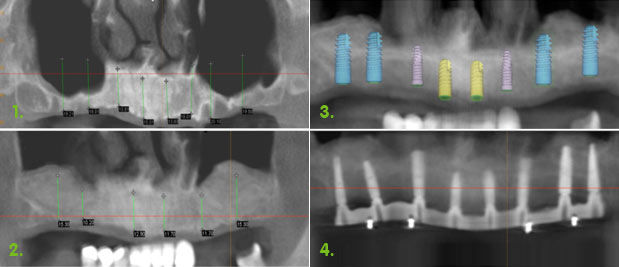

If you do not have enough bone we may need to give you more bone. With advances on modern techniques, with the correct case selection this is now quite predicable. If further bone is required this may be added at the time of implant placement or sometimes must be completed before the implant is placed.

The surgeon will place the bone graft under sedation. There are many sorts of graft material that we can use, but your own blood supply will infuse into the graft and your own cells will use the graft as a scaffolding to build your own new bone structure to replace the graft! A sinus graft is a particular technique where The surgeon will create a small window in the thin bone beside the top back teeth. inside the hollow of your sinus (cheek bone) there is a thin membrane, a little like that found under an egg shell. Gently this is lifted and the bone substitute is placed into the newly created space between the membrane and the sinus. The window is closed and after six months the graft is converted into your own bone. This allow the dentist to then place bigger and better implants to support your crowns, your denture or bridgework. Mechanically this increased support will increase the load distribution and contribute to a greater chance of success.